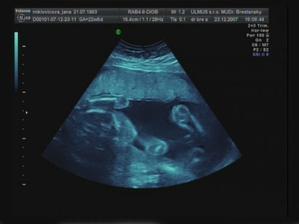

Emuška

Ahojte už som tu z 1,5cm som vyrástla na takúto krásnu slečnu moje meno je Emka a narodila som sa 4.4.2008 o 12:25 hod v Topolčianskej nemocnici vážila som 3510g a najviac na svete ma ľúbia maminka a ocinko